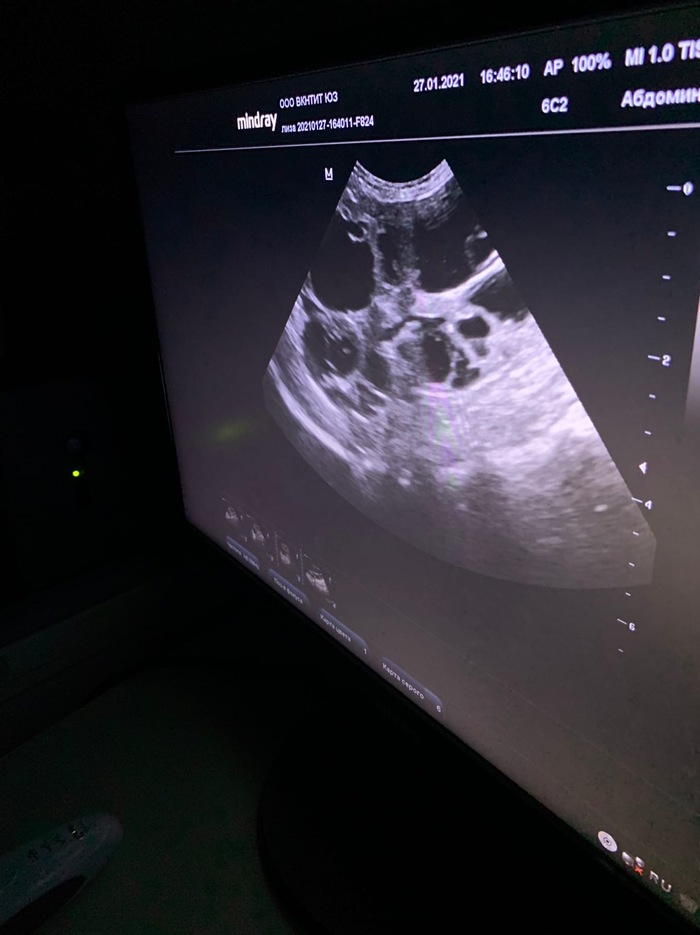

Что мы имеем: одна почка не функционирует от слова совсем, вторая в кистах, печень барахлит и до кучи анемия. Ей причиняет боль любое прикосновение, она грустная, но вет говорит поборемся..